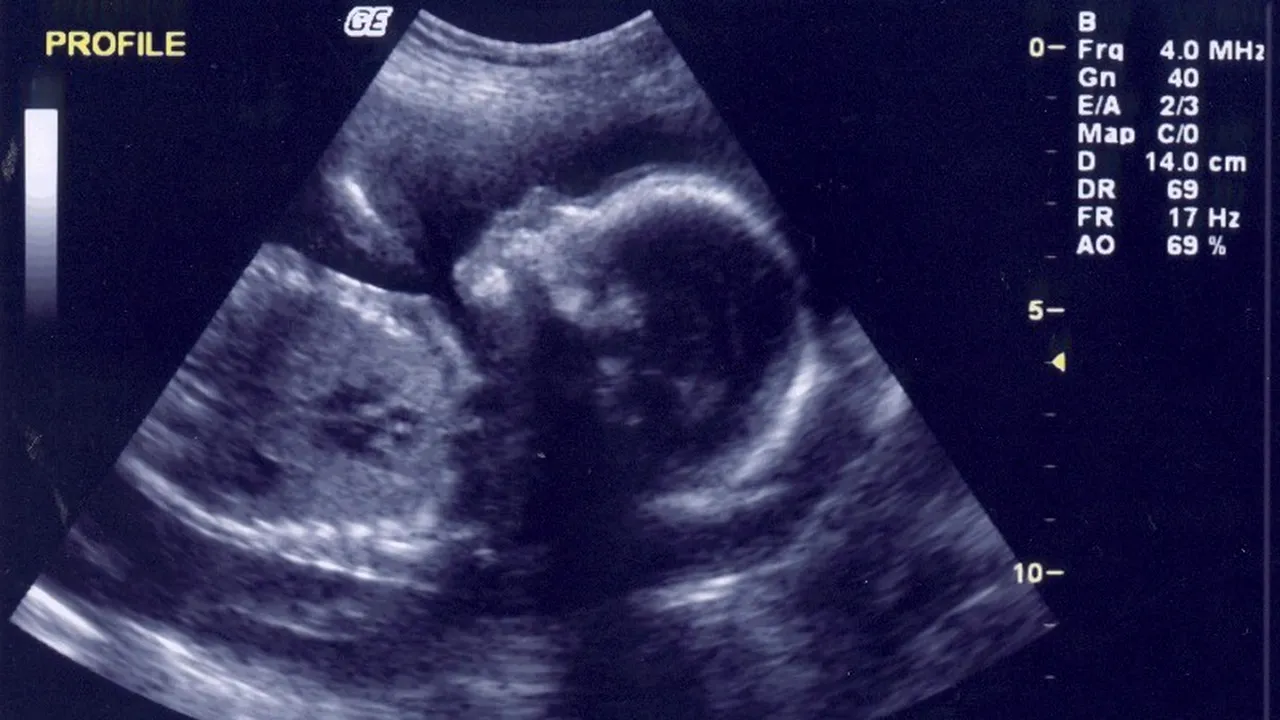

Oamenii de știință din Marea Britanie au primit aprobarea de a modifica genetic embrioni umani, procedura experimentală fiind autorizată de Autoritatea pentru Fertilizare Umană și Embriologie (HFEA), instituție ce reglementează etica și procedura fertilizării umane, potrivit bbc.com.

Studiile se vor desfășura la Institutul Francis Crick din Londra și au ca scop înțelegerea temeinică a momentelor inițiale ale dezvoltării vieții umane. Experimentele se vor face în primele șapte zile de după fertilizare și ar putea evidenția cauzele avortului spontan.

„Vrem să înțelegem genele necesare pentru ca un embrion uman să se dezvolte într-un copil sănătos. Motivele sunt infertilitatea și avorturile, care devin probleme din ce în ce mai prezente, dar nu sunt fenomene foarte bine studiate”, a afirmat cercetătoarea dr. Kathy Niakan pentru a motiva lansarea tehnicii de editare genetică a embrionilor umani. Kathy Niakan studiază de peste zece ani dezvoltarea embrionară, iar principala țintă a experimentelor ei este înțelegerea detaliată a primelor șapte zile ale creșterii. De-a lungul acestui interval de timp, ovulul fertilizat evoluează într-o structură de veziculă germinativă numită blastocist, formată din 200-300 de celule. Chiar și în acestă etapă de blastocist, unele celule îndeplinesc un rol specific – unele cresc mai departe pentru a se implanta în placentă, unele formează un sac membranos atașat de embrion, iar altele se grupează formând corpul fătului. În această perioadă, segmente din ADN-ul uman înregistrează o activitate intensă. Este probabil ca aceste gene să ne ghideze dezvoltarea primară, dar este neclar cum eșuează acest proces în cazul unui avort.